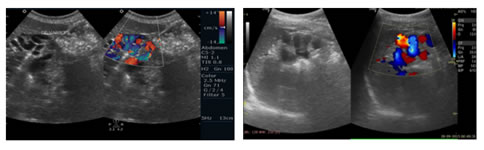

Figure 5:                                                                              Figure 6:

4

Figure 7:                                                                              Figure 8:

5

Figure 9:                                                                              Figure 10:

Figure 11:                                                                            Figure 12:

Figure 7: Spectral Doppler USG image: Showing Biphasic flow in Splenic vein; Figure 8: Gray scale and Colour Doppler USG image: Showing Cavernomatous transformation of Portal vein; Figure 9: Gray scale and Colour Doppler USG image; Figure 10: Showing Dilated Coronary vein with Hepatofugal flow; Figure 11: Gray scale and Colour Doppler USG image: Showing GEJ collaterals; Figure 12: Gray scale and Colour Doppler USG image: Showing Lienorenal collaterals; Figure 13: Gray scale and Colour Doppler USG image: Showing Recannalised Paraumbilical vein with hepatofugal flow; Figure 14: Colour Doppler USG image: Showing Absent Colour flow in Portal vein due to Thrombosis